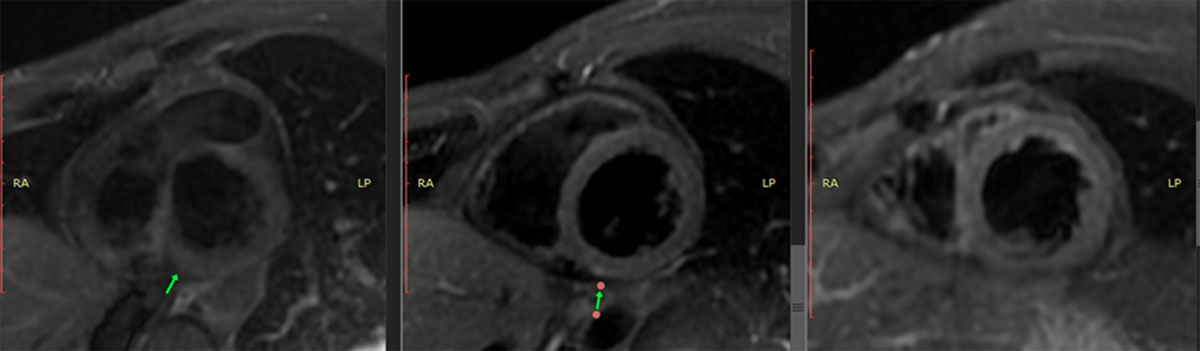

The presence of myocardial edema was also observed in the same inferior wall with inferoseptal extension (Figure 4). Late enhancement sequences revealed gadolinium uptake in the basal, medial, and inferior basal inferoseptal segments of the left ventricle, and the pericardium in its basal region (Figure 5). All of these findings are consistent with acute myocarditis.

Figure 4

Cardiac MRI with triple IR sequencing showing hyperintense signal, compatible with myocardial edema.